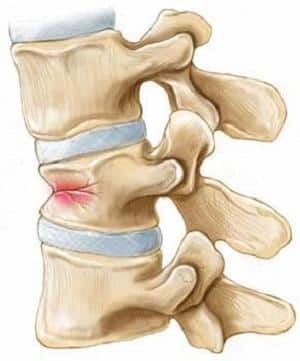

Компрессионный перелом позвоночника представляет собой повреждение, возникающее в результате сильного давления на позвонки, что приводит к их сжатию и деформации. Врачи отмечают, что такие переломы чаще всего возникают у пожилых людей с остеопорозом, а также у спортсменов и людей, занимающихся экстремальными видами спорта. Лечение компрессионного перелома зависит от его тяжести. В легких случаях может быть достаточно консервативной терапии, включающей покой, обезболивающие препараты и физиотерапию. В более серьезных случаях может потребоваться хирургическое вмешательство для стабилизации позвоночника. Важно, чтобы пациенты проходили регулярные обследования и следовали рекомендациям врачей, чтобы избежать осложнений и ускорить процесс восстановления.

В случае компрессионного перелома происходит одновременное сжатие и сгибание одного или нескольких позвонков, в результате чего страдают не только мягкие ткани, но и костные структуры.

По степени тяжести травмы выделяют 1, 2 и 3 степени, основываясь на степени повреждения и уменьшении высоты позвонка. Уменьшение высоты может составлять как минимум одну треть, а в случае более серьезных травм — половину и более.